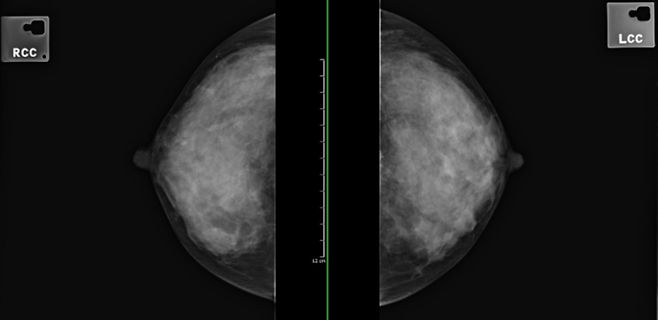

- 40대~: 매년 유방촬영술(mammography)